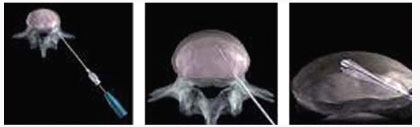

전방 요추체간 유합술 (Anterior Lumbar Interbody Fusion)

- 수술시 출혈이 적다.

- 수술 창상이 적다

- 수술 후 조기보행이 가능

- 수술 후 인접 척추체에 영향이 적다